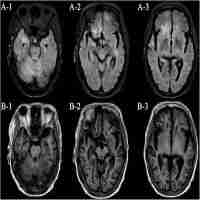

| Abstract | Ethyl methanesulfonate is a mutagenic, alkylating agent and considered harmful to humans at levels greater than a certain threshold; however, the toxicity at high doses remains unclear. We report a case of a Japanese man who presented with status epilepticus, rhabdomyolysis, pancytopenia, and hair loss after accidental ingestion of a massive amount of ethyl methanesulfonate. The patient completely recovered with critical care, including multiple antiepileptic drugs, renal replacement therapy, blood transfusion, granulocyte colony-stimulating factor therapy, and antibacterial/fungal prophylaxis. The case indicates that ethyl methanesulfonate causes neurotoxicity, hepatotoxicity, hematotoxicity, and renal toxicity, which can be successfully treated with appropriate palliative therapies. |